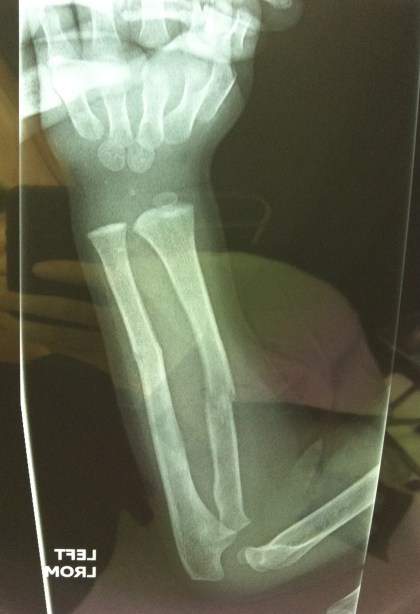

This month has been insane and we are hardly a week in. I’m trying to cherish every moment, the good and the bad and the heartbreaking. Let’s start at the beginning. Last Monday, that gorgeous little curly red headed boy decided to pretend to be Iron Man and take a flying leap off of a play structure (Thomas now uses the word “structure” when describing what happened). The result is a broken arm (fractured both the radius and ulna) and a green cast.